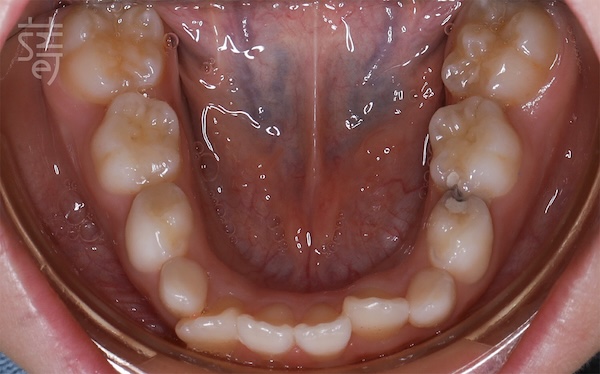

柯醫師也注意到,小緹的牙弓偏窄,其實和她長期鼻過敏有關。當孩子長期鼻塞時,就會改用嘴巴呼吸。久而久之,舌頭往下掉,沒辦法頂住上顎,失去自然支撐力,牙弓就會越來越窄。

Dr. Ko also noticed that Ti’s upper arch was narrowing — a pattern often linked to her long-standing nasal allergies. When children can’t breathe well through their nose, they naturally switch to mouth breathing. Over time, the tongue sits low instead of resting against the palate, removing the gentle support that helps shape the upper jaw. Slowly, the arch becomes narrower.

為了從根本改善,小緹接受齒性擴弓,慢慢把上顎調回理想的卵圓形,預留空間給未來的恆牙。同時,柯醫師也建議媽媽帶她做耳鼻喉科檢查,讓呼吸與口腔同步調整。

To address the root cause, Ti began a gentle dental expansion to guide her upper arch back toward a healthy, oval shape, creating room for her future permanent teeth. Dr. Ko also encouraged her mother to visit an ENT specialist, ensuring Ti’s breathing and oral development could progress together.

柯醫師說明,兒童矯正和成人很大的差異是,要留心發育中各種牽動的因素,從呼吸、舌位到顎骨一起看,治療才會更完整。

As Dr. Ko explains, children’s orthodontics is different from adult treatment. You must look beyond the teeth — at breathing, tongue posture, and growing bones — because everything develops as one.